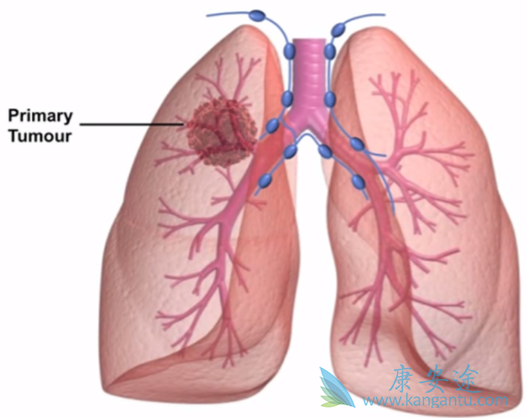

ALK阳性非小细胞肺癌(NSCLC) 的一线治疗方案充斥着多种靶向药物。Alectinib(艾乐替尼,Alecensa)已成为大多数这些患者目前的护理标准,但一线brigatinib(布加替尼,Alunbrig)的阳性结果有可能再次改变治疗现状。PROFILE 1014临床试验,我们看到克唑替尼(Xalkori)优于化疗。

但现在经过4年多的随访,我们可以看到,如果他们接受了正确的治疗,这些患者的生存率会有显着提高。在ASCEND-4研究中看到ceritinib(色瑞替尼,Zykadia)优于化疗,但最大的变化是Alex试验,Alectinib远远优于化疗,化疗不再是首选。Alectinib作为我们首选的一线选择,是一种优良的,耐受性良好,高效的药物。

名为B7461001的试验中,针对不同类型的ALK阳性肺癌患者,一线使用Lorlatinib(劳拉替尼,Lorbrena)有效率最高达90%,更重要的是,对于克唑替尼耐药的患者来说,继续使用Lorlatinib,有效率69%;而对于三种ALK抑制剂都耐药的患者,Lorlatinib也有很好的效果,有效率高达39%。综上,可选药物有:克唑替尼、艾乐替尼、布加替尼、色瑞替尼、劳拉替尼。